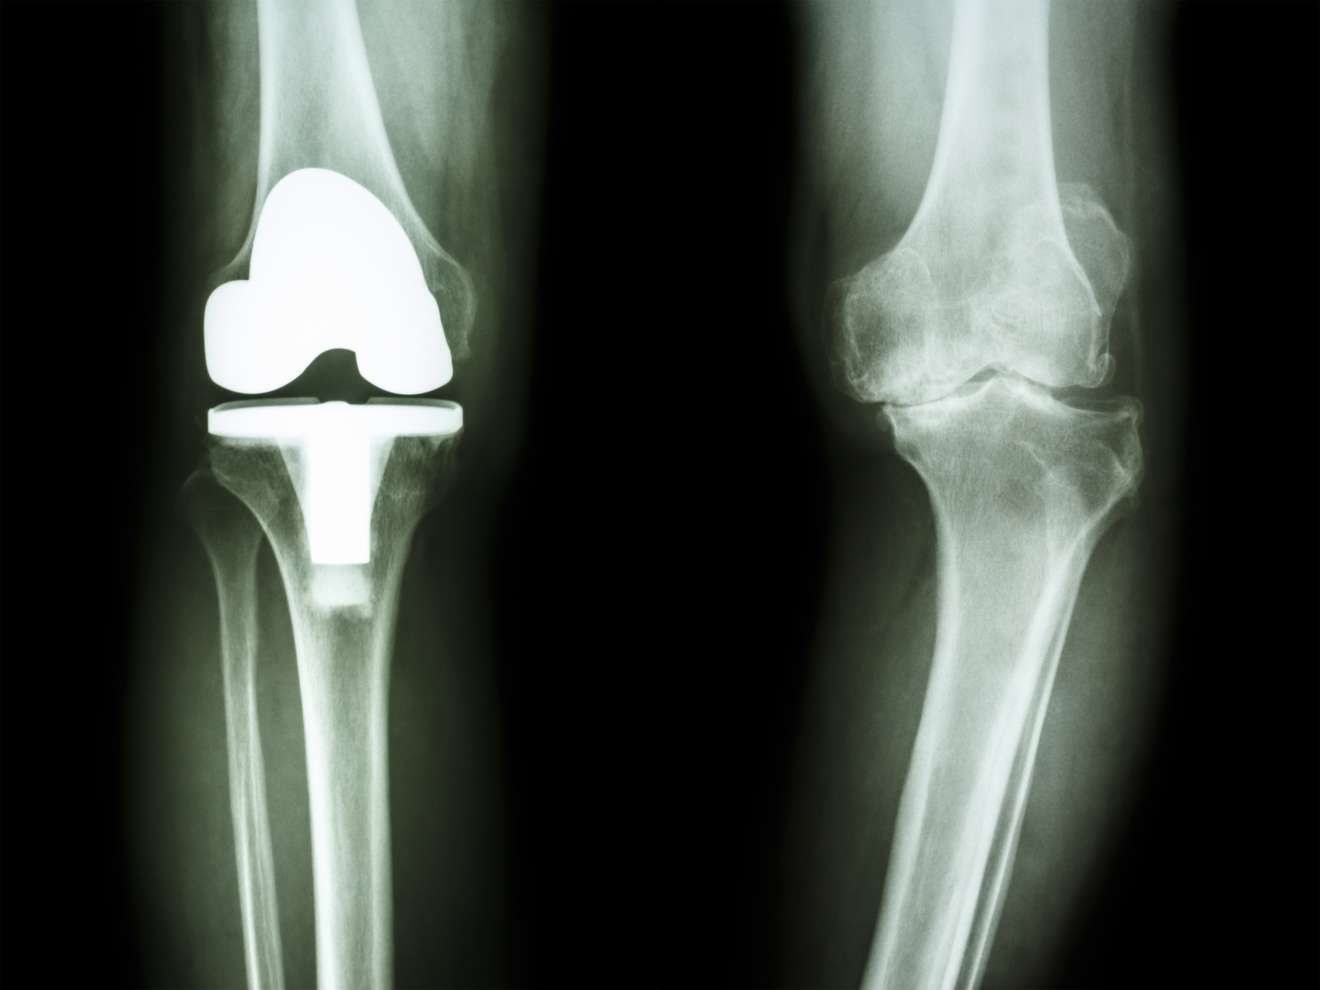

エビデンスに基づいた人工膝関節置換術後の理学療法

TKA後のROM・筋力・疼痛改善のポイント、歩行障害の原因やADLや復職,スポーツ復帰に対してエビデンスに基づいて学ぶセミナーです。